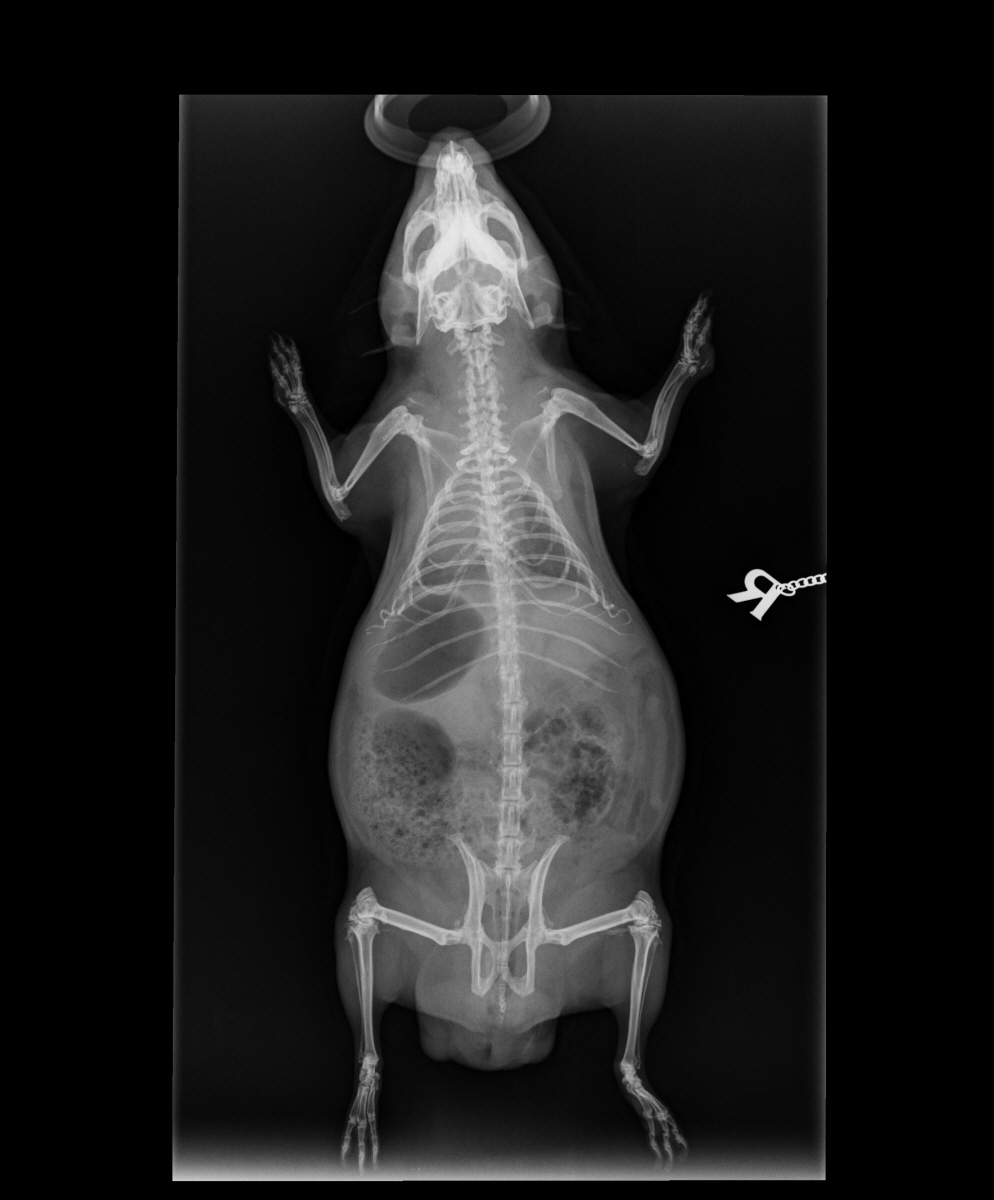

We showed you Neville’s x-rays on the A to Z in 2022; you can see those here in detail, especially at the top of the page — it’s easy to see his round bladder stones between his hip and his spine (high up in his bladder).

I had my x-rays done the other week, to see if I had arthritis. I do, but not too bad at present. What Mummy and Dr Rebekah got very interested in, though, was my ribcage.

Most of this is pretty normal. You can see little white patches on many of my joints: ankles, elbows, shoulders, hips and knees. That’s arthritis.

My ribcage is okay where it is bone, but where it is cartilage it looks unusual. In the top picture, at the bottom of the rib cage, about level with the bottom of the letter R (for right), you can see some curly things. Those should be straight, and curve back towards my ribs like the ones above! Dr Rebekah reckons that they didn’t develop properly before I was born, and the next image gives more clues.

It’s not easy to see those floating rib cartilages in this view, but you can tell they don’t join up below. And if you compare it with Neville’s you might see why.

If you follow Neville’s breast bone down, it ends in a bone which takes the line of the others. Now look at mine. It points down!

Mummy knew very early on that I had a lump under my chest and she asked Dr Rebekah about it, who said it was just my breastbone. It’s out of place, and not supported by those twirly cartilages at all. Dr R said I probably was a big baby, too big for my young mum, who had already had two girls just before she started growing me. So I didnt quite grow fully, or at least got a little squished.

It doesn’t cause me any trouble, although it may explain some weakness. But do you remember when we said for letter N, never use a harness on a guinea pig because it damages their ribs? You can see here how fragile our ribs are generally, and mine in particular.